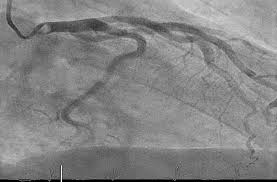

Total coronary revascularisation.

This 47 yr old diabetic individual had class II –III angina for the past 2 yrs. Risk factors were moderate hypercholestomia & moderate hypertension. ...